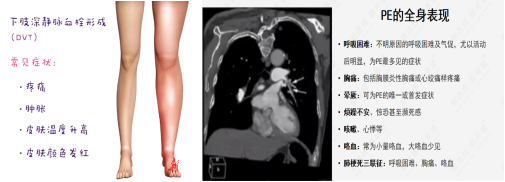

以肺血栓栓塞癥(PTE)為主要臨床類型的肺栓塞(PE)和深靜脈血栓形成(DVT)合稱為靜脈血栓栓塞癥(VTE),是同一疾病在不同階段、不同部位的兩種重要臨床表現(xiàn)形式。臨床上諸多科室的患者均存在VTE風(fēng)險(xiǎn),其發(fā)病隱匿、臨床癥狀不典型,容易誤診、漏診,一旦發(fā)生,致死和致殘率高; DissolVE-2 研究表明[1],我國的外科住院患者 VTE 中、 高風(fēng)險(xiǎn)比例高達(dá)86.1%,內(nèi)科患者 VTE 高風(fēng)險(xiǎn)比例為 36.6%;文獻(xiàn)報(bào)道美國每年死于VTE患者25萬至30萬。除了死亡之外,未能及時(shí)處理的VTE,多數(shù)不能幸免于深靜脈血栓后遺癥(PTS)的發(fā)生,造成患者長期病痛,影響生活和工作能力,嚴(yán)重者可致殘。

肺栓塞(PE)的觀察及護(hù)理:

下肢DVT最嚴(yán)重的并發(fā)癥是肺栓塞。肺栓塞急性期病人應(yīng)絕對臥床休息10~14天,床上活動時(shí)避免動作幅度過大,禁止按摩、擠壓或熱敷患肢,保持大便通暢,避免屏氣用力的動作,以防血栓脫落。若病人出現(xiàn)胸痛、呼吸困難、血壓下降等異常情況,提示可能發(fā)生肺栓塞,應(yīng)立即囑病人平臥,避免做深呼吸、咳嗽、劇烈翻動,同時(shí)給予高濃度氧氣吸入,并報(bào)告醫(yī)師,配合搶救。